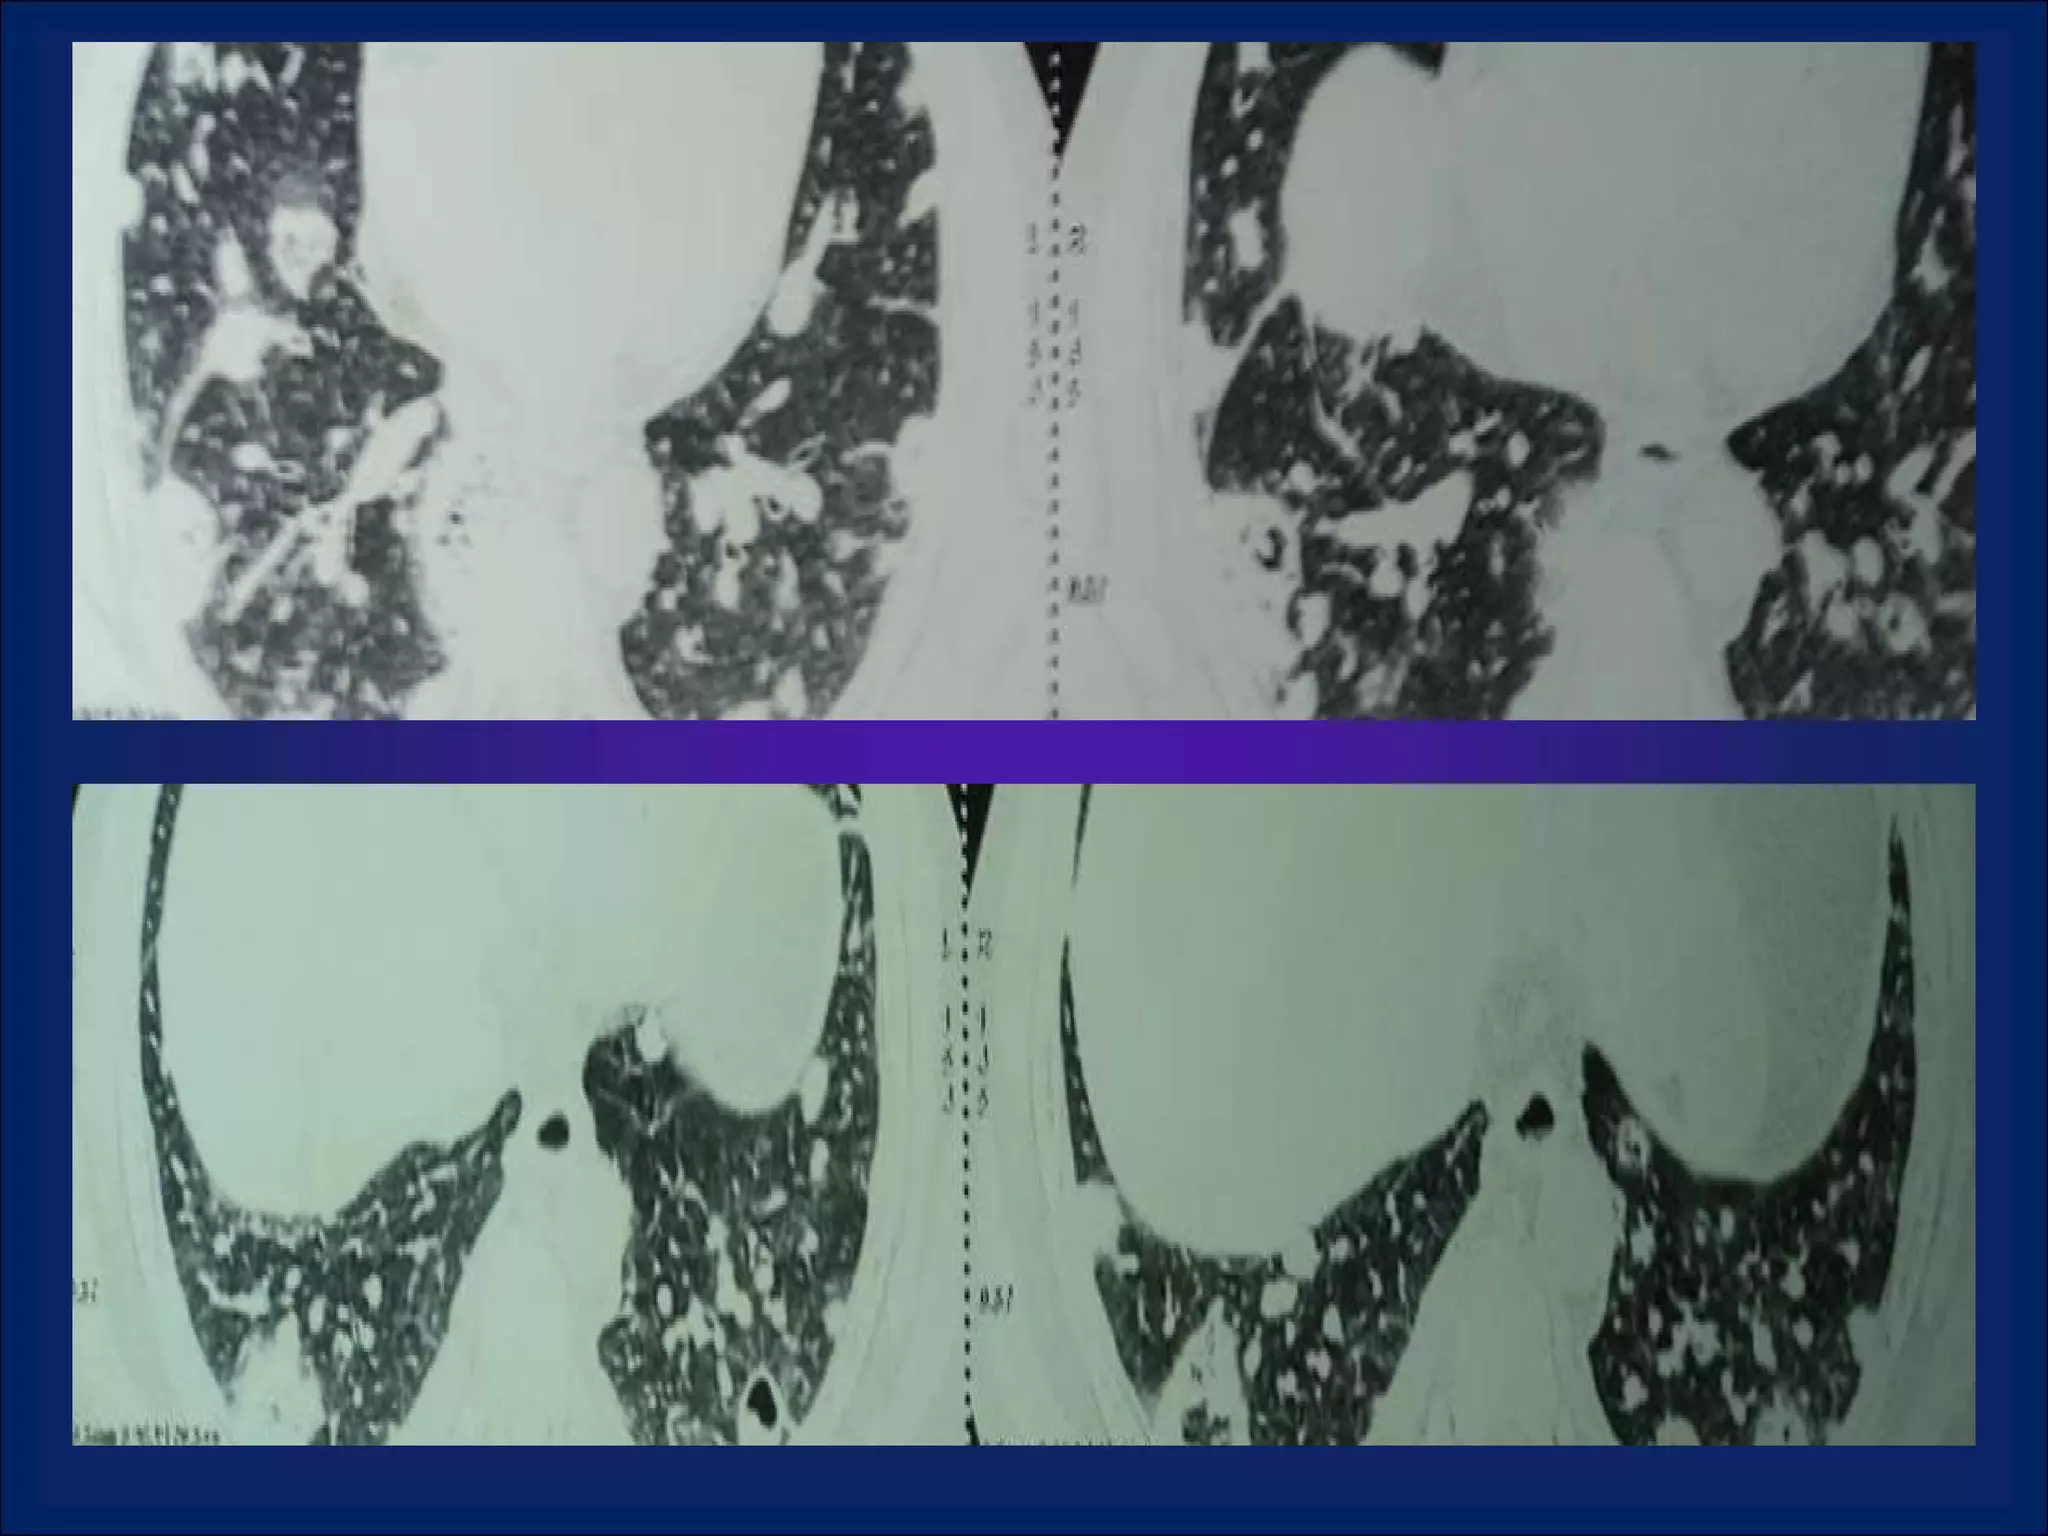

Imaging: Multiple Pulmonary Cavitary Lesions

LOOKING  AT  CAVITIES What is the anatomic distribution?  Is It single or multiple?  If multiple , are they focally located or diffusely seen in multiple lobes of both lungs? Is are the characteristics of the cavity? Is the cavity wall thick or thin? Is the interior lining nodular, shaggy, or smooth? Are there any other associated radiographic abnormalities?